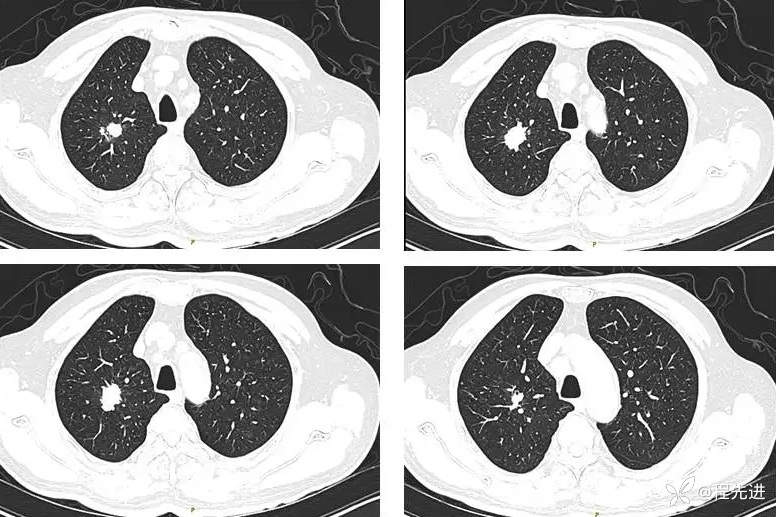

患者性别:男

患者年龄:70岁

简要病史:因“体检发现肺结节10余天”入院,患者平时无明显咳嗽、咳痰,胸闷胸痛咯血、呼吸困难

既往史:吸烟40年,平均每天30支;戒烟10年。高血压、糖尿病。

指脉氧 97% 一般情况可,其他阴性,实验室检查:NSE:20.56 ng/ml↑